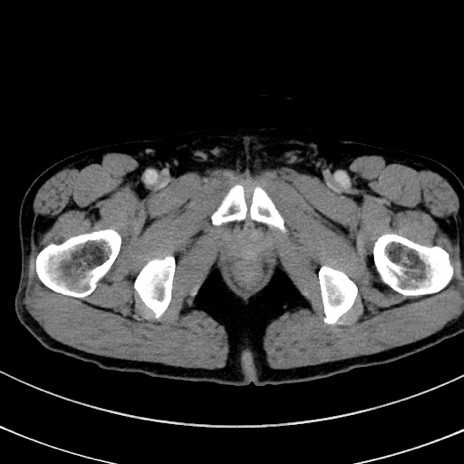

症例8(横断像)

【症例】 60歳代男性

【主訴】 黒色吐物

【現病歴】 4日前から嘔気自覚、2日前の朝食後にも嘔気あり、自分で手で嘔吐反射起こし嘔吐したところ血が混ざっていたため受診。

【既往歴】 5年前汎発性腹膜炎を伴う急性虫垂炎で手術、高血圧、前立腺肥大症、高脂血症

【身体所見】 腹部正中に手術癩痕あり 腹部平坦・軟圧痛なし膨満感あり

【データ】WBC 8400、CRP 4.54